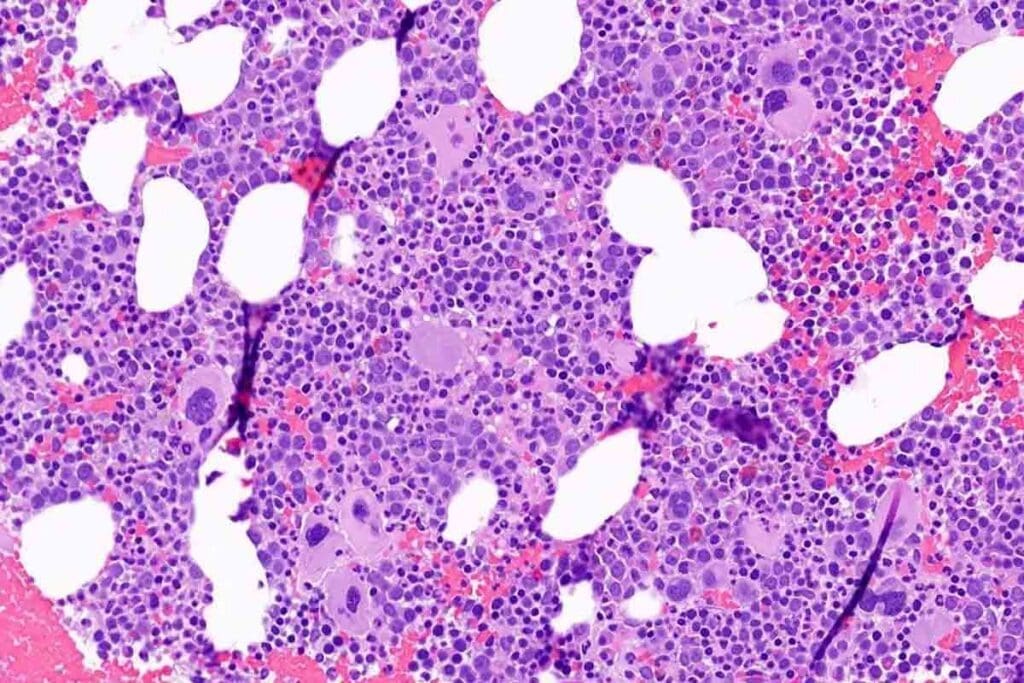

Bone Marrow Histology in Aplastic Anemia

Bone marrow histology gives us key insights into aplastic anemia. It’s vital for diagnosing and understanding how severe the condition is.

Hypocellular and Acellular Marrow Patterns

In aplastic anemia, the bone marrow shows hypocellular or acellular patterns. This means there’s a big drop in cell numbers. Studies show that how low the cell count is can tell us how severe the anemia is.

Residual Hematopoietic Islands

Even with low cell counts, some blood-making islands can be found. These islands hint at the marrow’s ability to recover. Knowing about these islands helps doctors predict how well a patient might do.

Bone Marrow Biopsy Techniques and Interpretation

Bone marrow biopsy is a key test for aplastic anemia. It lets doctors see how many cells there are and what they look like. It’s important to read these results well, as they help confirm the diagnosis and guide treatment.

The outlook for aplastic anemia depends on how bad it is and how well it responds to treatment. Knowing about the bone marrow’s state is key to choosing the right treatment and predicting how well a patient will do.